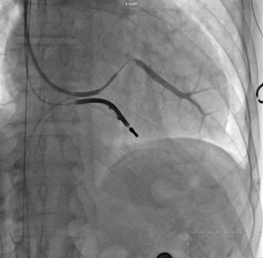

冠狀靜脈逆行造影

?“它的技術(shù)難點在于左室電極的植入”。朱彬介紹,除了常規(guī)的由于心臟擴大變形所致的冠狀靜脈竇口位置改變,自身冠狀靜脈解剖異常等問題外,傳統(tǒng)的左室電極安置后存在起搏位點選擇性小,起搏時容易出現(xiàn)膈神經(jīng)或膈肌刺激、起搏高閾值、為保證穩(wěn)定性將電極植入心尖而出現(xiàn)心尖部起搏,為避免心尖部起搏避開心尖位置但卻出現(xiàn)電極不穩(wěn)定術(shù)后移位等諸多問題。而左室四極電極導(dǎo)線由于可以有多個起搏位點和多種起搏向量的選擇,可一次性解決上述難題,能做到“電極植入心尖,起搏心底”。綜合患者具體情況,為提高手術(shù)成功率,降低手術(shù)風(fēng)險,朱彬決定在該手術(shù)中使用目前國內(nèi)最新型的左室四極電極。